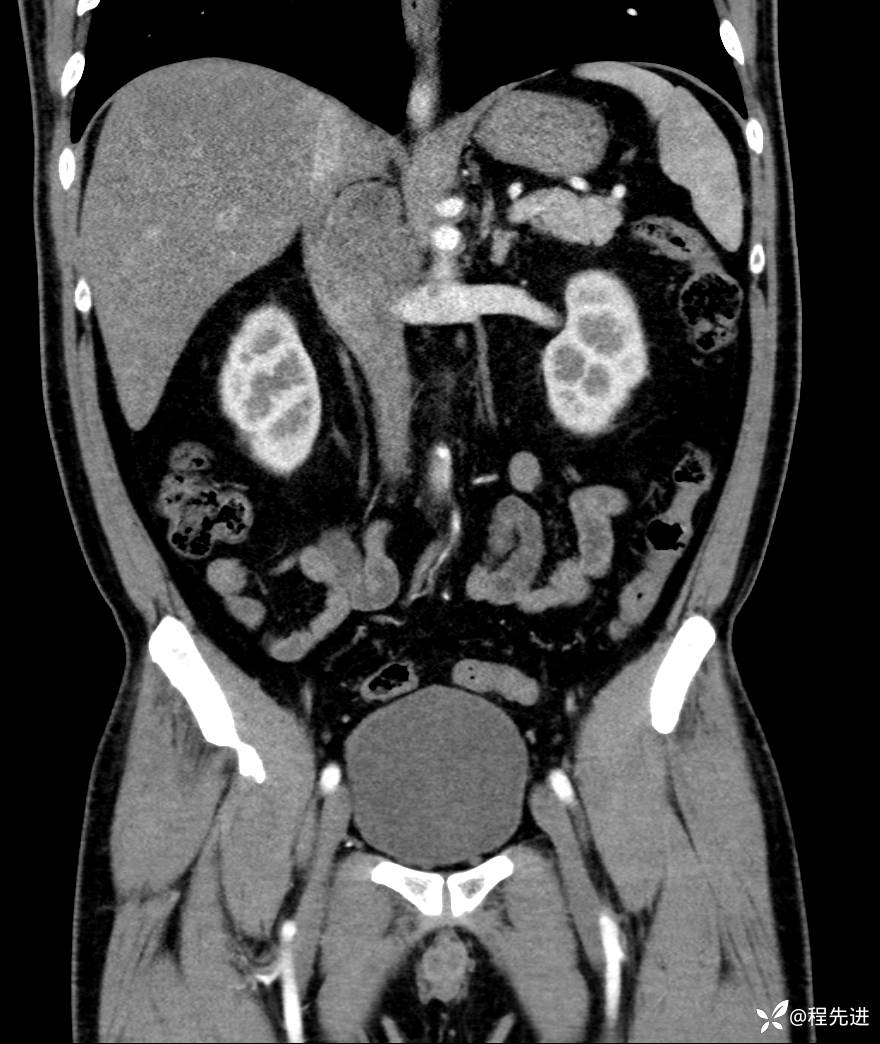

【腹盆】特别精彩病例|发现腹膜后肿物1月余

主诉:发现腹膜后肿物1月余

现病史:患者1月余前查体,行超声检查提示:后腹膜囊实性肿块;慢性胆囊炎伴胆囊内结石;无腹痛腹胀,不伴腹泻发热等;偶感腰背部酸痛。

CT平扫+增强: